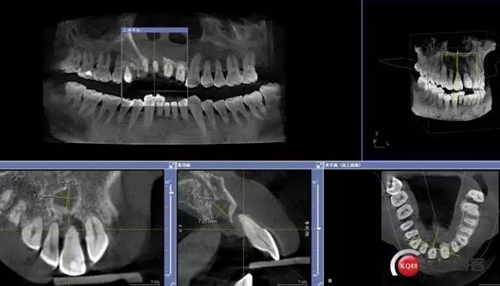

上前牙即刻種植+GBR+囊腫摘除病例 科貿(mào)嘉友收錄

患者:王XX 年齡:42 上前牙松動數(shù)年,從未做過任何處理,今來院就診;檢查:CBCT示上前牙區(qū)顎側(cè)一大小約7x7mm囊腫;治療計劃:即刻種植同期摘除囊腫

術(shù)前CBCT